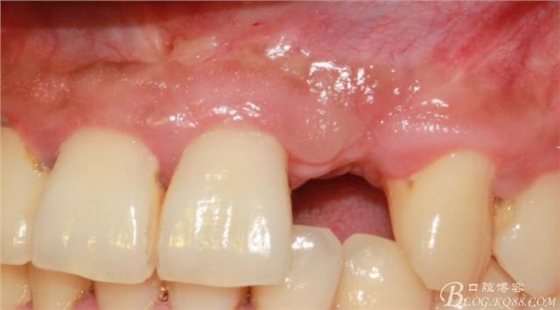

事實證明,我的做法沒有錯誤,一個月后,軟組織健康愈合。鄰牙軟組織沒有退縮。

再次翻瓣。